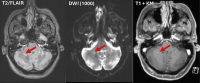

Abbildung 4: Patient B: cMRT von Mai 2022 (FLAIR-Sequenz, DWI-Sequenz, T1-Sequenz mit KM): neu aufgetretene Kleinhirnläsion links (blauer Pfeil) mit Diffusionsrestriktion (grüner Pfeil), fleckig inhomogene KM-Speicherung der Läsion („milky way sign“, roter Pfeil)